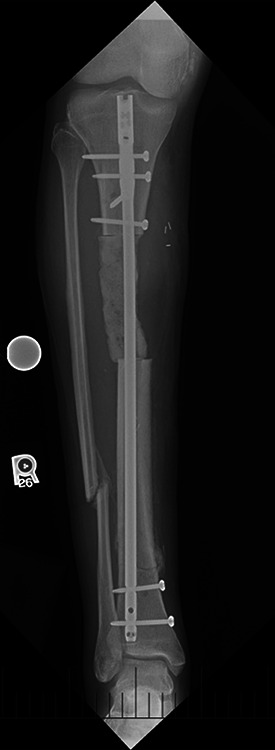

Case description: A 42-year-old male presented for complex right tibia reconstruction following a type IIIB open tibia fracture with a 92-mm bone defect. The bone defect was initially managed with an all-internal bone transport nail system (PRECICE bone transport). At the 13-month follow-up, the patient presented with a broken lengthening nail, varus limb deformity, and nonunion at the docking site. The nail components were extracted sequentially, and a burr hole was created in the distal segment of the nail through the nonunion site to facilitate removal. The residual varus deformity and tibial shaft nonunion were managed with a hexapod frame.

Conclusion: The IMLN was successfully removed without compromising limb reconstruction. By sequentially removing the components of the nail and altering the distal portion of the implant through the nonunion site, safe removal of the implant without further bone loss was achieved.